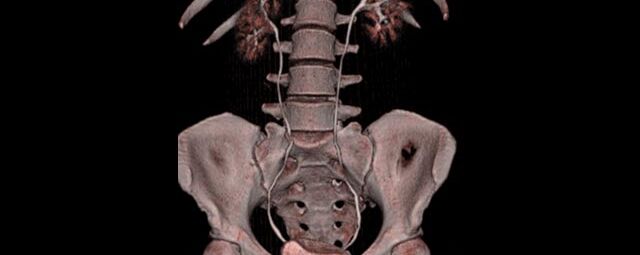

Abdomen (Bauch und Becken)

• Diagnostik von entzündlichen und tumorösen Erkrankungen der Bauchorgane

• Diagnostik von akuten Notfällen wie Darmverschluss, Hohlorganperforation oder Traumafolgen

• Darstellung der großen Gefäße zur Erkennung von Gefäßverschlüssen (z. B. Mesenterial - Arterienembolie oder Einengungen von Gefäßen (z. B. Nierenarterien)

• Darstellung und Therapieplanung von Aneurysmen (CT- Angiographie)

• Virtuelle Kolonographie zur Darstellung des Dickdarmes z. B. bei Kontraindikation zur Darm-Spiegelung oder nur unvollständig durchführbarer Koloskopie.

Wirbelsäule

• Darstellung von Frakturen, Tumoren und Bandscheibenveränderungen

Extremitäten

• bei komplizierten Frakturen z. B. in der Nähe von Gelenken oder im Bereich der Handwurzel und Fußwurzel